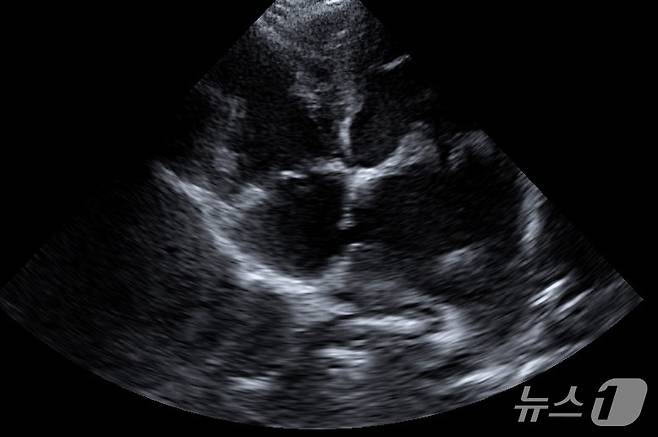

심장 초음파 검사 결과, 사랑이는 기존 MMVD로 인해 좌심방 압력이 극도로 상승된 상태였다. 이 과정에서 좌심방과 우심방을 나누는 심방중격 부위가 과도한 압력을 견디지 못하고 터져 있었다.

사랑이는 선천적인 심장 기형은 아니었다. 주치의는 오랜 시간 누적된 심장 부담으로 인해 후천적으로 발생한 심방중격 파열로 판단했다.